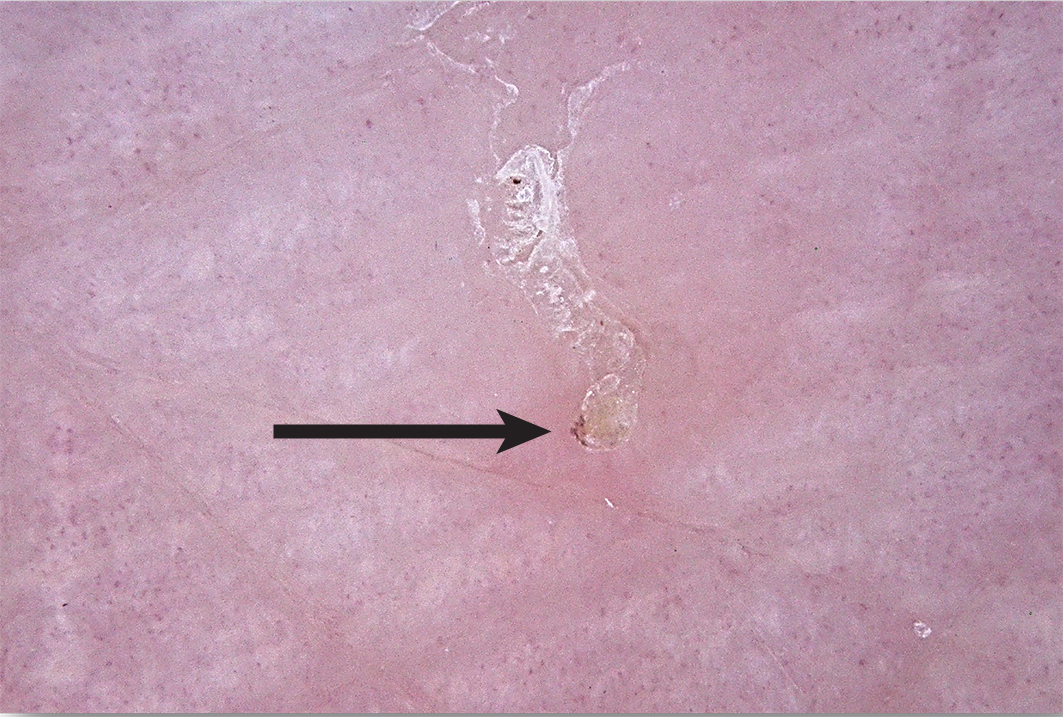

Box 4 – Dermatoscopic image of a scabetic burrow, arrow pointing to the “delta sign” indicative of the mite's head

Scabies is generally a clinical diagnosis. Direct visualisation of a fresh skin scraping with 10% potassium hydroxide under light microscopy can confirm the diagnosis (Box 3, A and B); however, this is invasive and can be unreliable and impractical, especially in resource‐poor settings. The use of dermoscopy can reveal serpiginous burrows (representing the burrowing path of the adult female mite). Burrows are short, silvery‐grey, thread‐like cutaneous trails ranging about 3 to 7 mm long and 0.4 mm wide. It may also be possible to see a triangular or “delta” sign within the burrow, indicative of the mite's head (Box 4). Translucent ovoid eggs can also be seen as “mini triangular signs” under dermoscopy. Excoriation and secondary infection can alter the clinical presentation and obscure the dermoscopic presentation of scabies.6,20